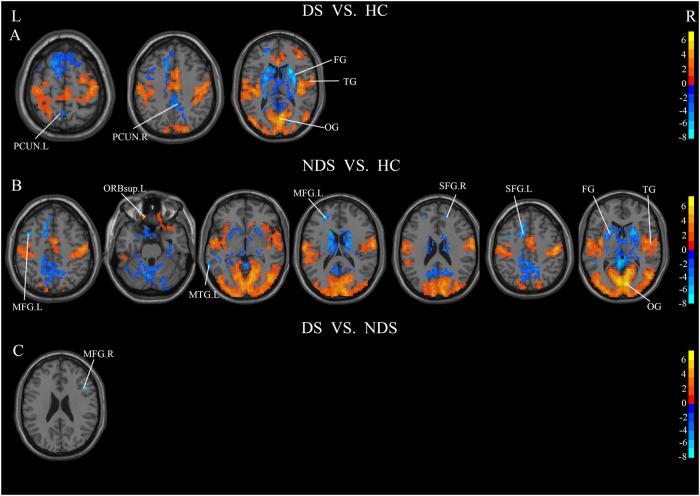

Deficit schizophrenia (DS) is a subtype of schizophrenia (SCZ). The polygenic effects on the neuroimaging alterations in DS still remain unknown. This study aims to calculate the polygenic risk scores for schizophrenia (PRS-SCZ) in DS, and further explores the potential associations with functional features of brain. PRS-SCZ was calculated according to the Whole Exome sequencing and Genome-wide association studies (GWAS). Resting-state fMRI, as well as biochemical features and neurocognitive data were obtained from 33 DS, 47 NDS and 41 HCs, and association studies of genetic risk with neuroimaging were performed in this sample. The analyses of amplitude of low-frequency fluctuation (ALFF), regional homogeneity (ReHo) and functional connectivity (FC) were performed to detect the functional alterations between DS and NDS. In addition, correlation analysis was used to investigate the relationships between functional features (ALFF, ReHo, FC) and PRS-SCZ. The PRS-SCZ of DS was significantly lower than that in NDS and HC. Compared to NDS, there was a significant increase in the ALFF of left inferior temporal gyrus (ITG.L) and left inferior frontal gyrus (IFG.L) and a significant decrease in the ALFF of right precuneus (PCUN.R) and ReHo of right middle frontal gyrus (MFG.R) in DS. FCs were widely changed between DS and NDS, mainly concentrated in default mode network, including ITG, PCUN and angular gyrus (ANG). Correlation analysis revealed that the ALFF of left ITG, the ReHo of right middle frontal gyrus, the FC value between insula and ANG, left ITG and right corpus callosum, left ITG and right PCUN, as well as the scores of Trail Making Test-B, were associated with PRS-SCZ in DS. The present study demonstrated the differential polygenic effects on functional changes of brain in DS and NDS, providing a potential neuroimaging-genetic perspective for the pathogenesis of schizophrenia.